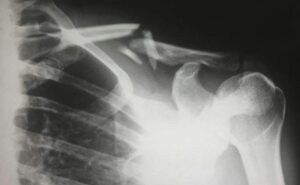

أصيبت امرأة صينية تعانى من نقص حاد فى فيتامين د نتيجة الإفراط فى استخدام واقى الشمس بكسر فى العظام لمجرد التقلب فى سريرها، حيث أبلغ أطباء مستشفى شيندو للطب التقليدى فى تشنجدو، الصين، مؤخرا عن حالة غير عادية لامرأة محلية تبلغ من العمر 48 عاما، أصيبت على ما يبدو بكسر فى العظام لمجرد التدحرج فى السرير، ووفقا للدكتور لونج شوانج، أظهرت الفحوصات التى أُجريت فى المستشفى أن مستويات فيتامين د لدى المرأة، التى لم يُكشف عن هويتها، كانت منخفضة للغاية، مما أدى إلى تسريع فقدان العظام وتسبب فى ظهور هشاشة عظام حادة.وكشفت تحقيقات أخرى أن المريضة كانت تتجنب أشعة الشمس منذ طفولتها، ونادرا ما كانت ترتدى قمصانا قصيرة الأكمام، وتحرص على وضع واقى الشمس دائما عند الخروج، وقد عُرضت حالتها كتحذير لعشاق واقى الشمس الذين قد يُفرطون فى استخدامه، مما يؤثر على صحة عظامهم، وفقا لموقع oddity central.